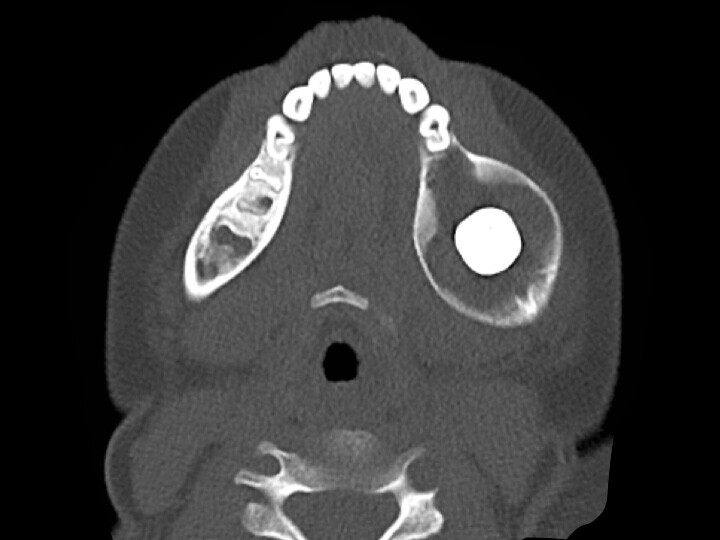

Large cyst surrounding tooth in the mandible

The most serious disease of the mouth is oral cancer, and any lesions that are found to be malignant (cancerous) usually need to be surgically removed. Benign (non-cancerous) lesions are also usually surgically removed as they can cause damage to surrounding tissues and often the benign diagnosis requires the lesion to be removed and sent to a pathologist to examine under a microscope. This includes cysts (fluid filled lesions) and tumors (solid lesions). Both can result in swelling, pain and infection. They can also increase in size, affecting nearby teeth and causing destruction of the jaw bone.